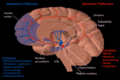

- Basal ganglia

- Includes: Nucleus caudatus, putamen, pallidum, subthalamus, substantia nigra

- Part of the forebrain.

- Caudate nucleus + putamen = striatum.

- Pallidum + putamen = lenticular nucleus.

Schematic overview (WC/blausen staff)

- Basal ganglia 1.jpg